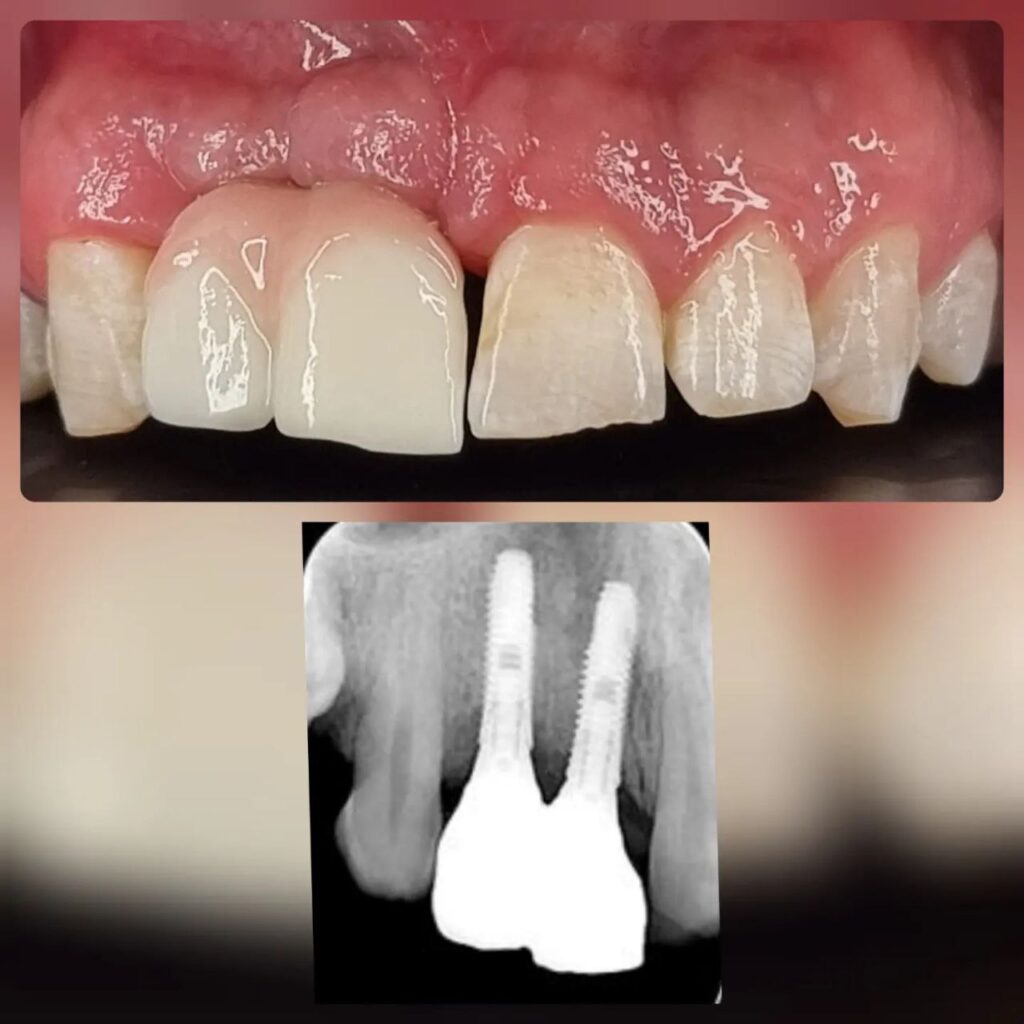

کاشت ایمپلنت دندان

اطمینان حاصل کردن از اینکه دندانهایتان به نحوی زیبا و طبیعی جایگزین شدهاند، از اهمیت بسیاری برخوردار است. ایمپلنت دندان به عنوان یک روش درمانی دائمی در دندانپزشکی شناخته میشود که حاصل آن، یک دندان زیبا و طبیعی در دهان شما خواهد بود.

هرچند که این روش درمانی هزینهی بیشتری نسبت به روشهای دیگر دارد، اما ارزش زیبایی که ایجاد میکند، قابل انکار نیست. ایمپلنتها به قدری شبیه به دندانهای طبیعی هستند که به سختی میتوان آنها را از دیگر دندانها تشخیص داد.